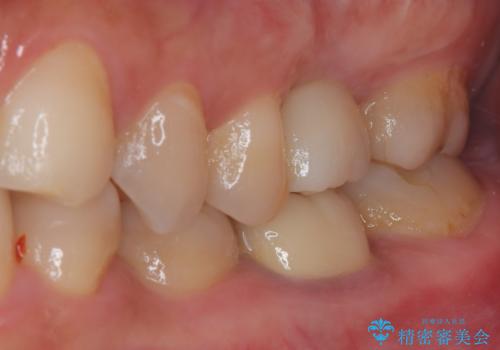

インプラント治療をきっかけに、銀歯を全てセラミックに替えていきました。

人の目を気にせずに、大きく口を開けて笑えるようになりました。